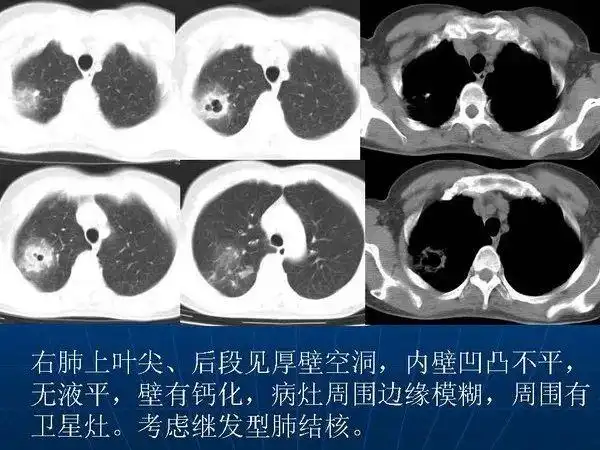

各型肺结核的典型影像表现

肺结核ct影像表现

肺结核及其肺部ct影像特征

肺结核的薄层ct征象树芽型的病理意义